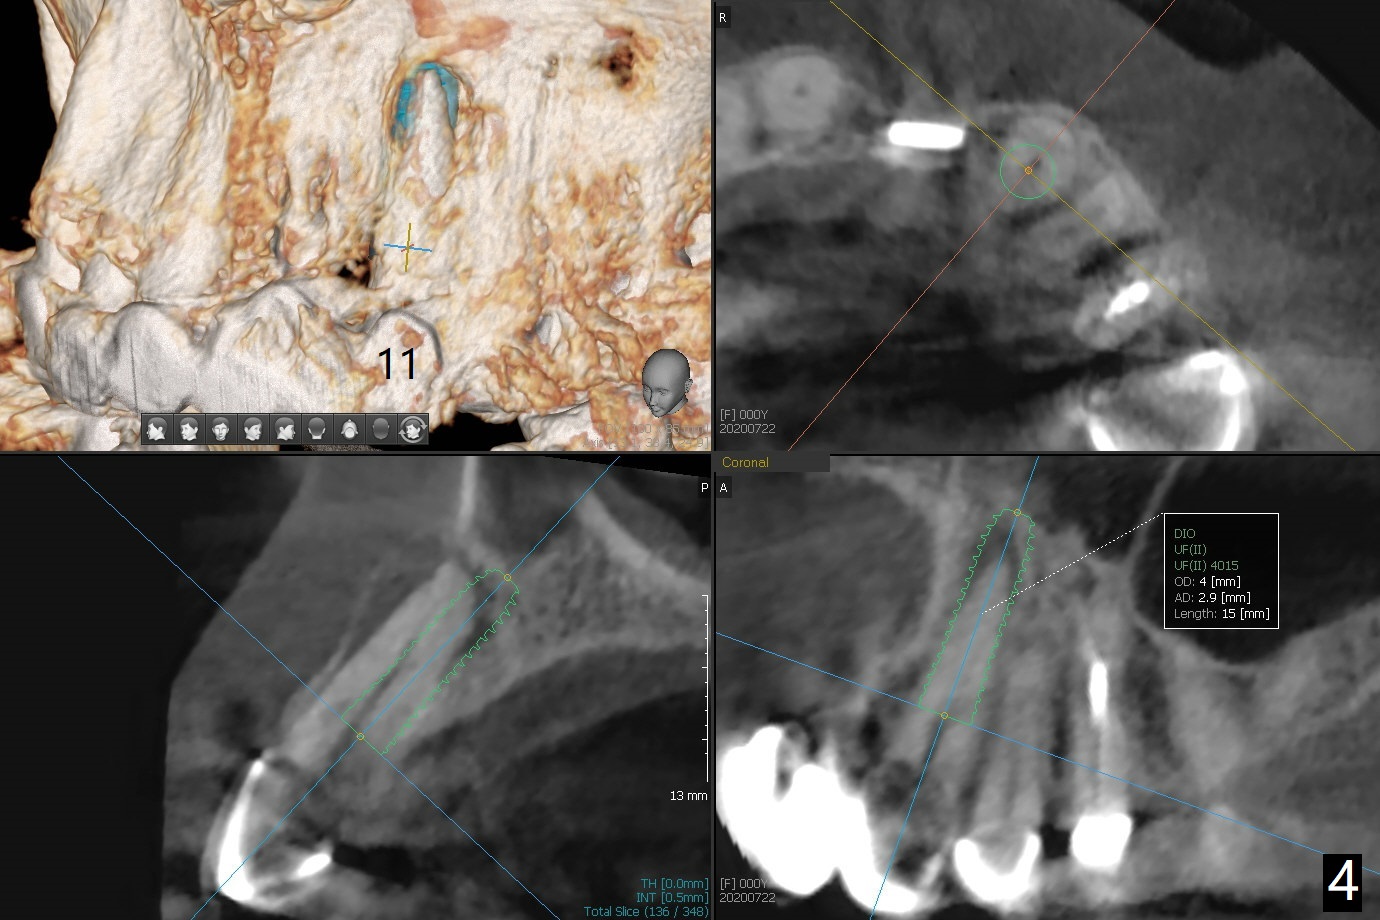

今天来一位57岁女,“前牙桥快掉了” (图一:7-11,桥在尖牙(11)端松动明显),不明白为什么左上中,侧切牙唇侧带有托牙树脂(*),影响局部卫生(^)。全景片(图二),CT(图三)显示刀柄植体,好像没有骨质吸收,但是修复体与基台脱离,树脂大概有美观作用。尖牙根尖瘘道(图一:>),阴影(图三 (B:颊侧),四)表明牙齿似乎无法保留,其余牙齿命运等待桥撤除后决定。琼脂取模,模型已制备,简易stent尚未完成。明天一早病人回来治疗,抽血一管制备骨块和PRF膜。